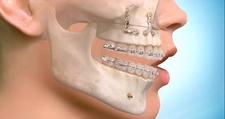

2. Cerrahi YöntemlerÇenenin yapısal bir problemi varsa, cerrahi müdahale gerekebilir. Aşağıdaki cerrahi yöntemler çenenin ileri alınmasında kullanılabilir: